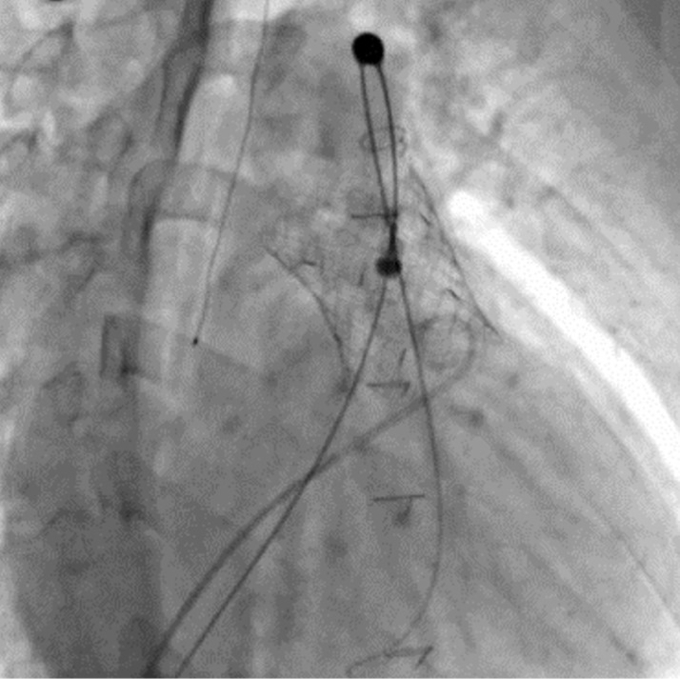

이번 시술은 소아청소년과 김기범·이상윤 교수팀이 주도했다. 경피적 폐동맥판막 치환술은 가슴을 열지 않고 허벅지 정맥을 통해 카테터로 인공 판막을 삽입하는 방식으로, 반복적인 개흉·개심수술을 대체하거나 수술 시점을 늦추는 치료 전략이다.

경피적 폐동맥판막 치환술은 이러한 한계를 보완하기 위해 도입됐다. 개흉을 하지 않기 때문에 회복 기간이 짧고, 입원 기간과 수술 관련 합병증 위험을 줄일 수 있다. 다만 해부학적 구조가 복잡하고, 기존 수술 병력이 있는 환자가 많아 고난도 시술로 분류된다.